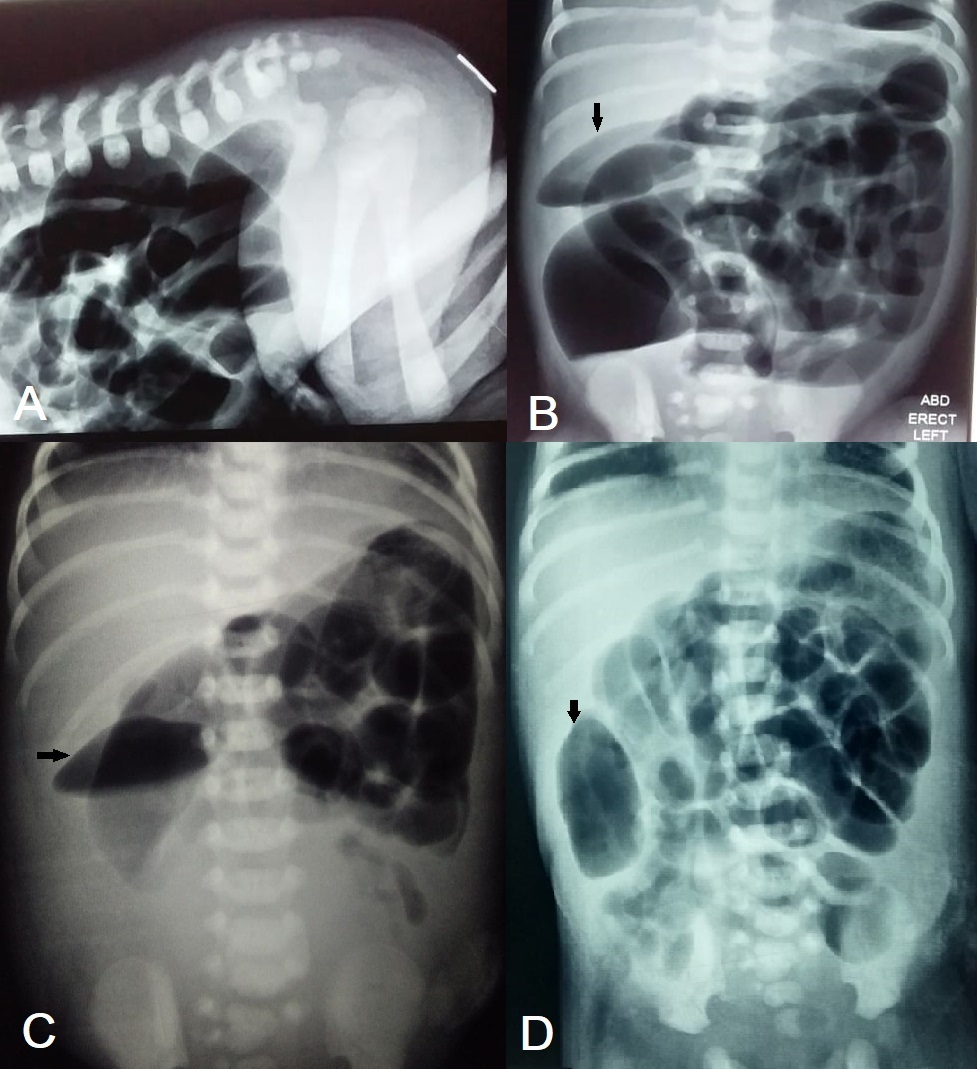

A 1-day-old male neonate, weighing 2.5kg, presented with failure to pass meconium since birth. The baby was born at term by spontaneous vaginal delivery. Antenatal follow-up and perinatal period were uneventful. On examination, the baby had abdominal distension and an imperforated anus. X-ray abdomen (prone cross-table lateral, and erect) showed a high variety of anorectal malformation (Fig. 1A, 1B). Ultrasound of the abdomen revealed normal kidneys. Echocardiography showed a small PDA. The laboratory tests were within normal ranges.

The repeat X-ray abdomen showed dilated small bowel loops. A fusiform area of bowel gas was noted in the right hemiabdomen that was also present on the initial radiographs. Laboratory tests showed a rising C-reactive protein and declining thrombocytes. The next day, repeated x-rays had the same findings; thus, the parents were counseled for reoperation. A segmental dilated portion of mid-ileum was found at exploratory laparotomy with proximal dilated loops and distal comparatively collapsed bowel(Fig. 2). The abrupt transition from normal bowel to segmental dilatation was absent. The dilated segment was resected, and an ileostomy formed—anastomosis avoided as the baby was getting septic. Serial biopsies were taken from the ileostomy site and colon that excluded Hirschsprung’s disease.

Antenatal and preoperative diagnoses are seldom, with most cases diagnosed at surgery.[4], [7] Abdominal X-ray, ultrasound, CT scan, and GIT contrast study may help the diagnosis preoperatively; though needs a high index of suspicion. It can mimic other surgical conditions on radiological investigations: pneumoperitoneum on an abdominal radiograph,[6] and duplication cyst on contrast imaging are few examples.[10] In the index case, we initially ignored the discrete fusiform gas shadow on the abdominal radiographs and noticed when the finding persisted on subsequent radiographs.

A) Cross table lateral film showing high anorectal malformation. B) Preoperative erect radiograph showing a fusiform area (arrow). C) Postoperative erect radiograph showing the same finding (arrow). D) Postoperative supine radiograph showing the same finding (arrow).